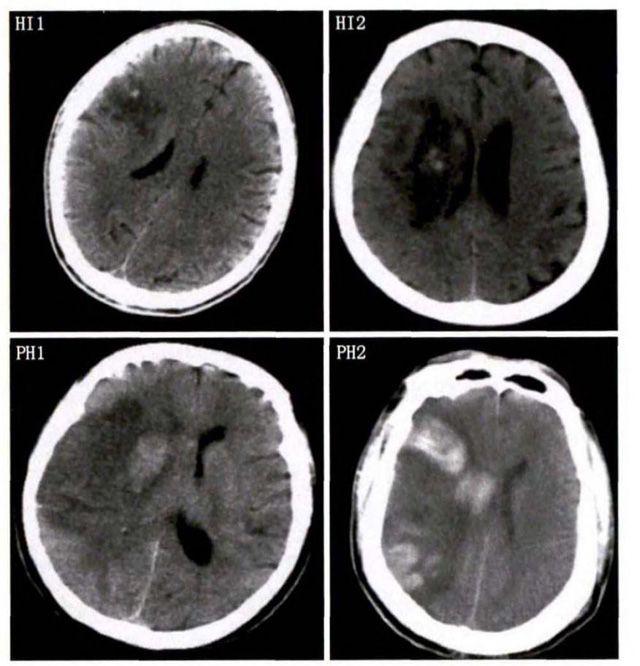

中、老年病患,有動脈粥樣硬化及高血壓病等腦卒中的危險因素,發病結合神經係統症狀和體征,應當考慮急性腦梗死的可能。再經腦CT/MRI發現梗死灶,或排除腦出血、炎症性疾病等,診斷即可確定。腦梗死有時頗似小量腦出血的臨床表現。腦栓塞在任何年齡都可以有發病的風險,可以在幾秒到幾分鍾達到頂峰。會有偏癱不能說話等局部神經功能損壞。栓子來源很種,可能是冠心病、心肌梗塞、心內膜炎等。合並心房纖顫,結合其他髒器官的支持診斷,CT跟磁共振都可以檢查確定栓塞位置數量還有是不是有伴發出血等問題。可以幫助診斷。

中老年有高血壓糖尿病發病病史,起病神經功能缺損症狀,臨床表現為腔隙綜合征,即可初步診斷本病。如果CT或磁共振證實有與神經功能缺失一致的腦部腔隙病灶, 符合大腦半球或腦幹深部的小穿通動脈病變,即可明確診斷。少數患者隱匿起病,無明顯臨床症狀,在影像學檢查時發現。